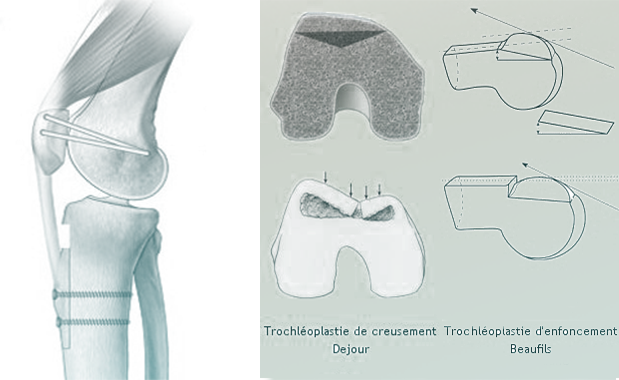

• Transposition de la Tubérosité Tibiale Antérieure (TTA) : Le chirurgien sectionne le bloc osseux de la TTA, le déplace vers l’intérieur et/ou vers le bas, puis le refixe avec deux vis. Cela permet de réaligner l’axe de traction du tendon rotulien.Trochléoplastie : Plus rare, cette technique consiste à creuser la trochlée fémorale lorsqu’elle est trop plate pour créer une gorge plus stable pour la rotule.